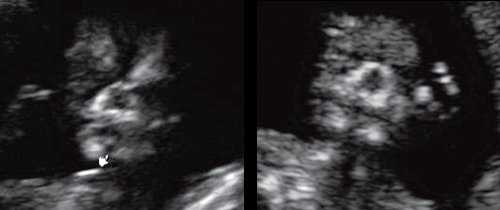

При патологии нижней челюсти (микрогнатии) в срок 11-14 нед беременности при изучении коронарного скана лица нижнечелюстной "промежуток" отсутствует, нижняя челюсть представлена единой, слившейся костной массой. Отсутствие нижнечелюстного "промежутка" (mandibular "gap") при эхографии в этот срок является маркером гипоплазии нижней челюсти (микрогнатии). Варианты отсутствия нижнечелюстного промежутка при микрогнатии при различных синдромах в срок 11-14 нед беременности представлены на рисунке 9.

Рис. 9. Отсутствие нижнечелюстного промежутка при микрогнатии, при различных синдромах нехромосомного генеза в 11-14 нед беременности.